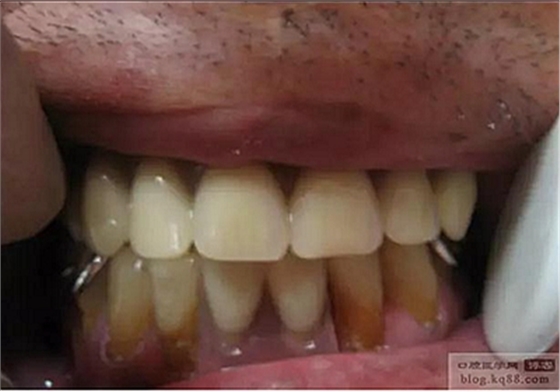

在上頜基托放置磁鐵的窩洞內(nèi)打洞.(樹脂排溢孔),將磁體放置到根樁銜鐵上,基托內(nèi)的窩洞內(nèi)放置自凝樹脂,然后將義齒戴入口內(nèi),待樹脂凝固后取下義齒,將多余樹脂打磨掉即可。

調(diào)頜后戴入口內(nèi)的照片,穩(wěn)固程度,美觀程度,豐滿度患者均很滿意。